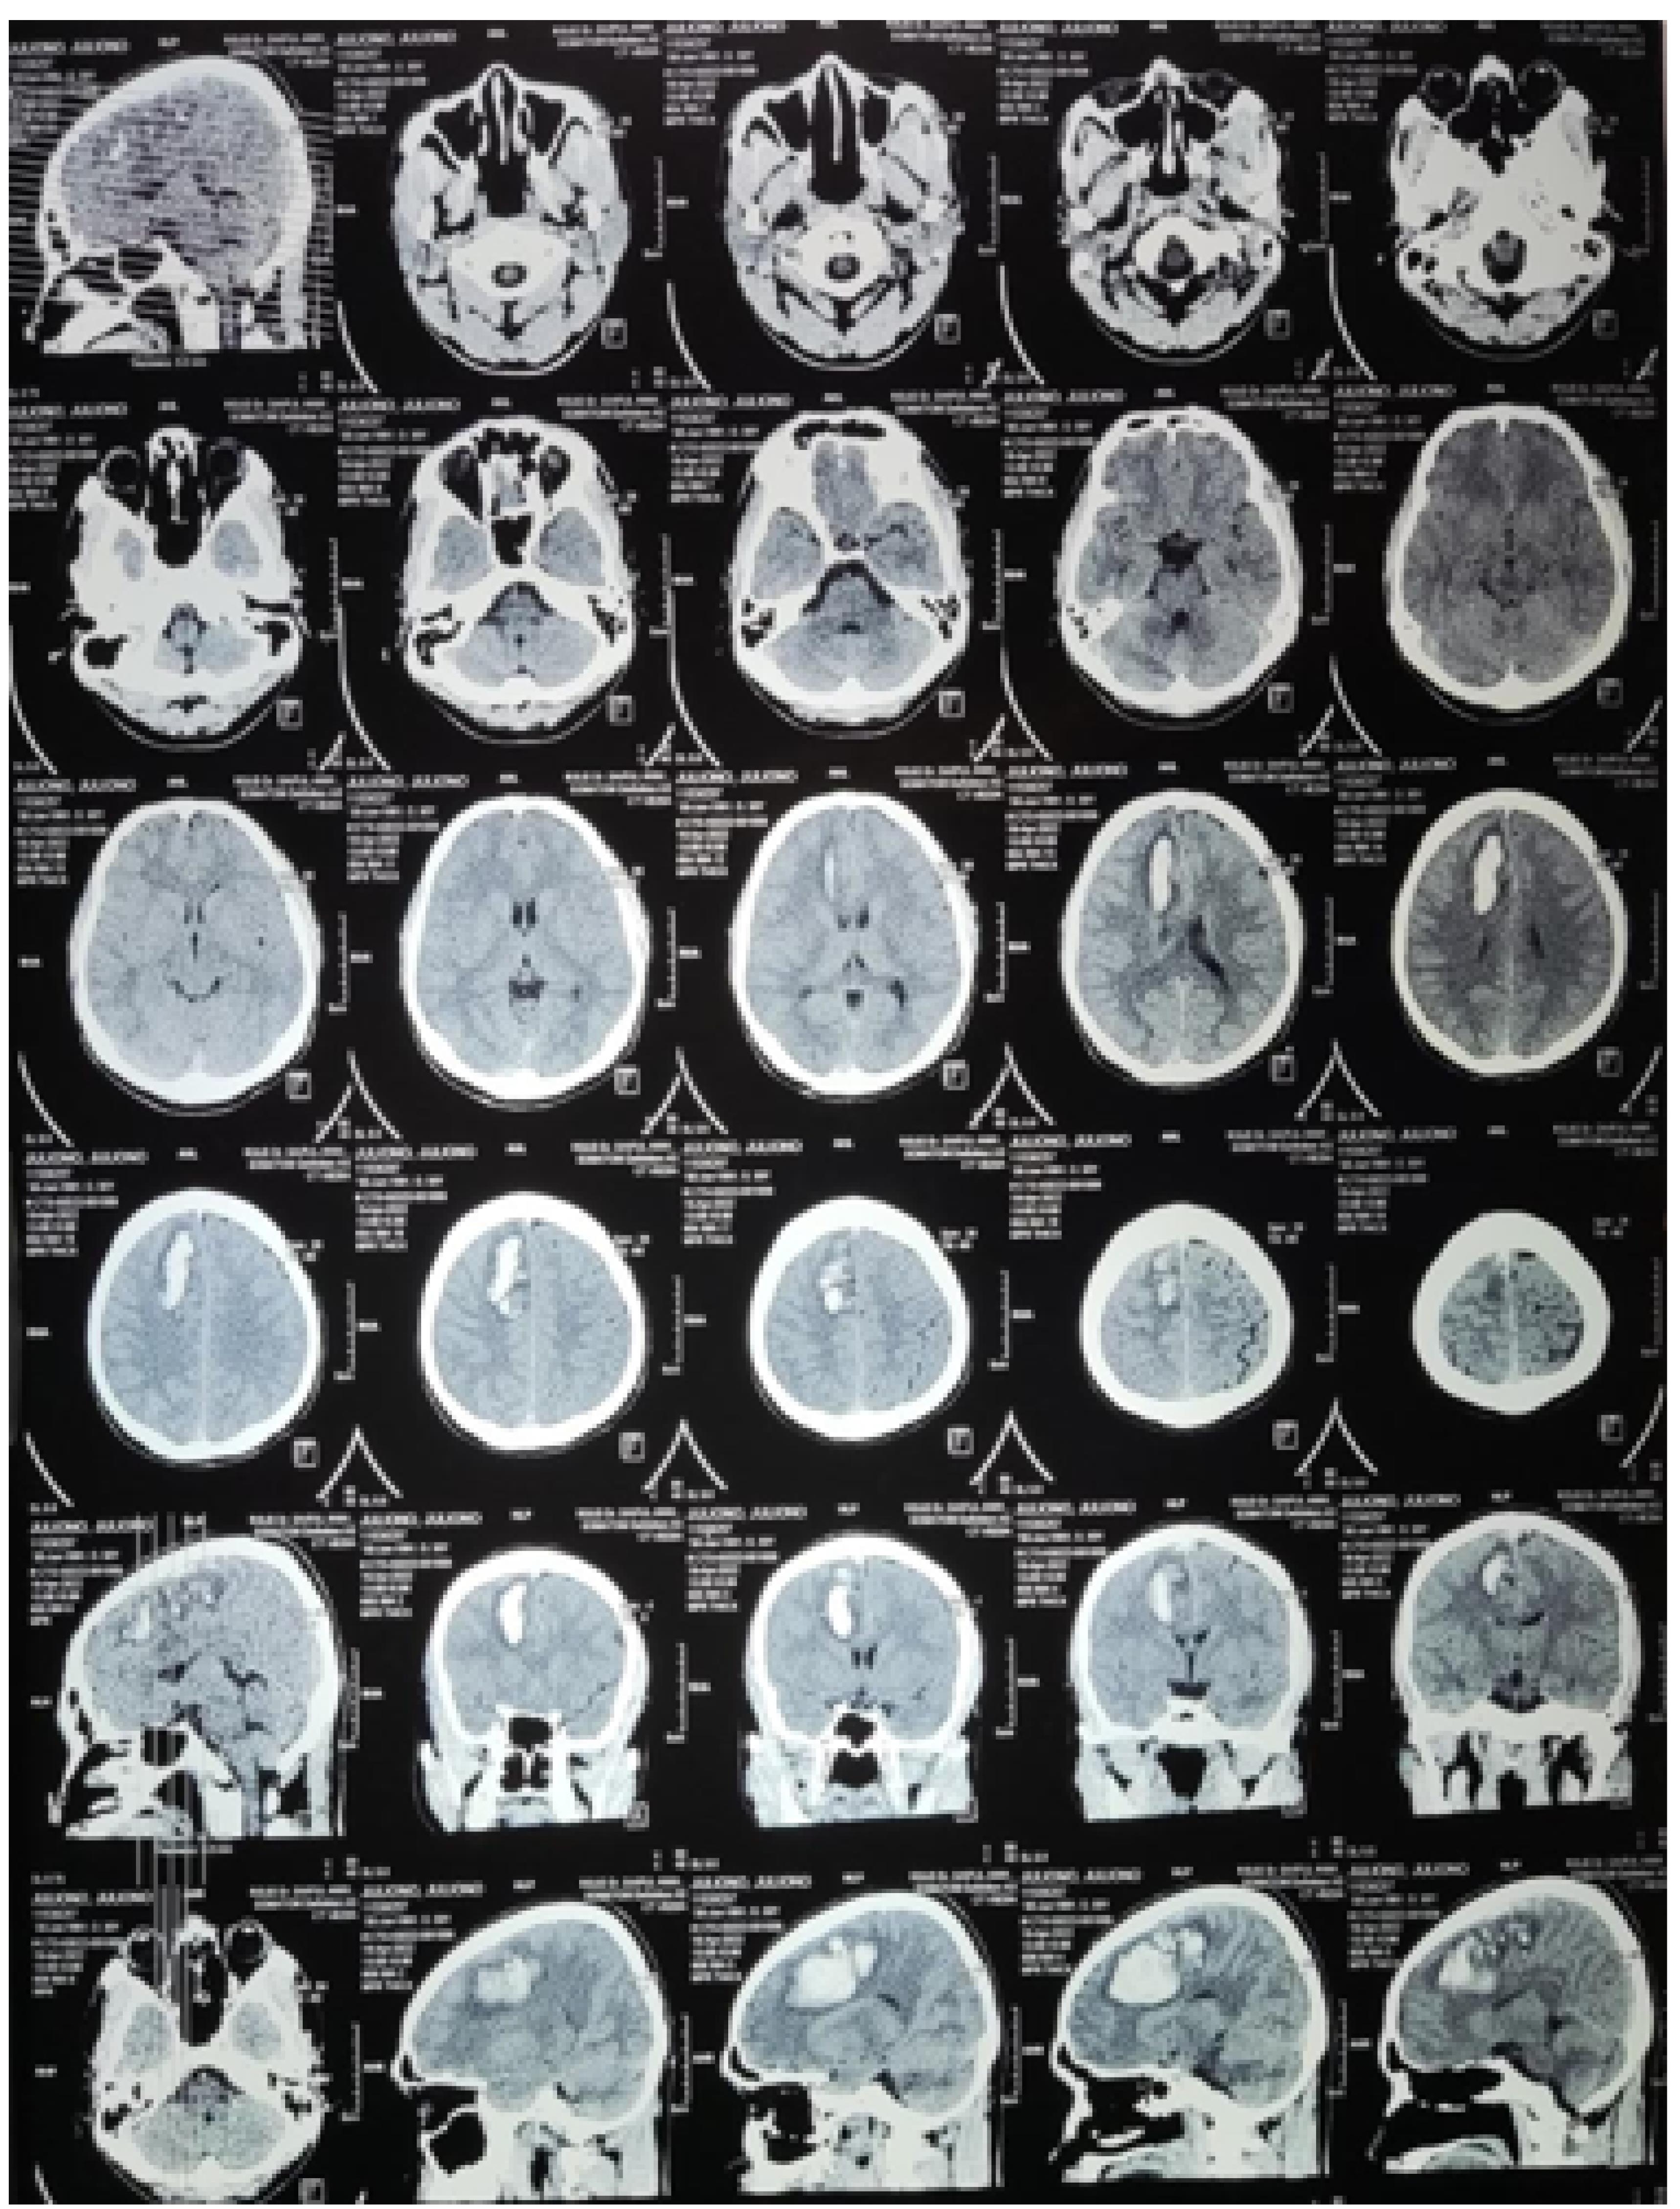

On physical examination general status, the patient is weak with Glasgow coma scale at 456, 123/84 mm Hg, with 70 times/minutes, respiration 20 times/minute, 36.7 °C and 98% on RA-SpO2. The patient was asked for head CTA. There was no abnormal cor and pulmo in normal boundary after X-ray chest-thorax examination (Figure 1). The ICH frontoparietal D vol 18 cc, with midline shift to left for 4 mm (Figure 2).

Figure 1.

Thorax examination on cor and pulmo boundary